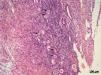

Each fresh fragment was immediately processed and evaluated using hematoxylin and eosin (H&E.) staining to quantify the follicular density, LIVE/DEAD staining5 to measure the follicular viability, and tissue culture with measurement of steroids in the medium to quantify the steroidogenic capacity. Tissue culture was performed only in the last seven cases (Figure 1).

Histological evaluationThe first tissue fragment was fixed in 4% paraformaldehyde (Merck, UN 2213 Paraformaldehyd, 4.1, III) and embedded in paraffin. Serial, 4-μm-thick sections were cut and stained with &E. The stained sections were examined using light microscopy (400× magnification), and the number of follicles was counted. For the area calculations, a macro camera was used that permits the user to choose the previously captured image, generate its calibration (the pixel (image unit) × millimeter relationship), and determine the structural measurements.6 The total number of follicles per mm3 was calculated using the following formula: Nt = (No×St×t), where Nt is the number of follicles, No is the mean number of follicles observed in 1 mm2, St is the total number of sections in 1 mm3 of tissue, and t is the section thickness.7

RESULTSA heterogeneous follicular distribution in the parenchyma, with a mean density of 361.3±255.4, 454.9±676.3, and 296.8±269.0 follicles/mm3 for FG, G30, and G180, respectively, was detected following H&E. staining (Figure 2). There were no differences observed between the groups (p = 0.46).

DISCUSSIONIn this study, we aimed to determine the quality of frozen-thawed ovarian tissue after cryopreservation by assessing different aspects of the recovered tissue, including follicular density, follicular viability, and steroidogenic capacity. Follicular density refers to the number of follicles present in the tissue per unit volume and can vary both with patient age and within the same patient. Follicular density has been proposed by several authors as a quality control criterion to evaulate tissue after thawing.1,12–14 According to Poirot et al.2, a mean density of 30 to 400 follicles/mm3 tissue is expected in patients aged 20 to 30 years; however, it should be noted that follicle distribution is usually not homogeneous throughout the ovarian cortex. In the present study, we detected mean follicular densities ranging from 300 to 460 follicles/mm3, in agreement with the literature, and confirmed the heterogeneous distribution of the follicles. The objective of the assessment of follicular density was to guarantee that the various tissue samples would contain an adequate number of follicles, which would allow for the evaluation of functional status and viability, as the fresh and frozen-thawed tissue sections stained with H&E. were obtained from side-by-side fragments.